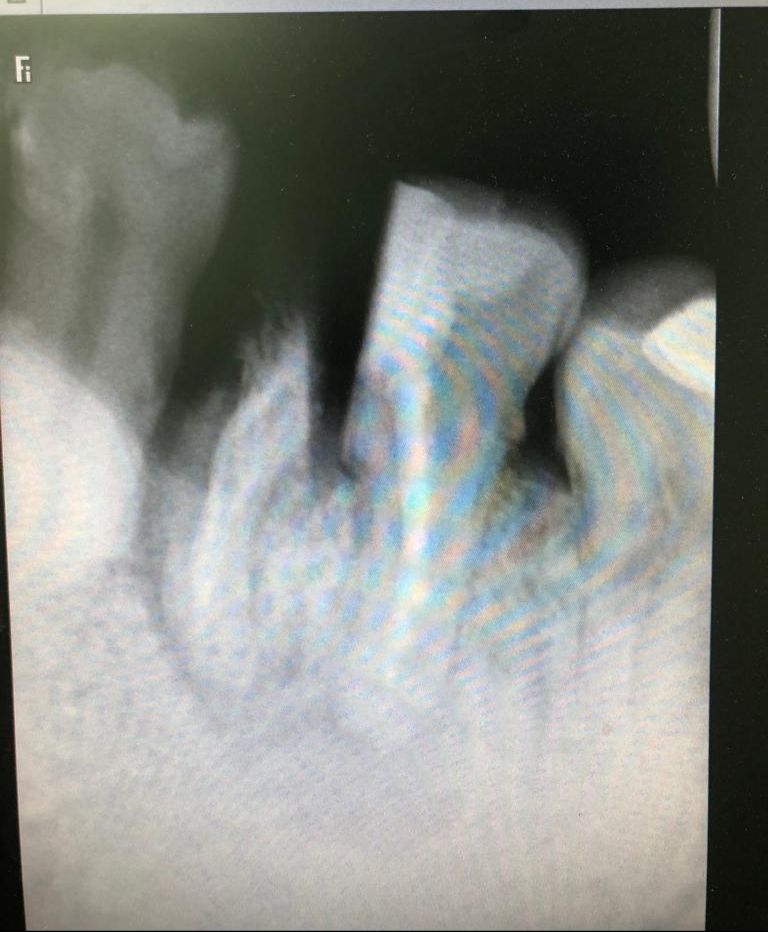

Paciente de mediana edad al que se le hizo una endodoncia con restauración de composite en el primer molar inferior o mandibular izquierdo hace varios años. Con el tiempo ha filtrado haciéndose caries en el interior de la restauración, e incluso en la raíz anterior o Mesial, en la cual se produjo una fractura vertical. Esto provocó el inicio de molestias en el paciente y es cuando acude a la clínica del Doctor Faus. Tras estudio radiológico, y ante el estado y molestias de la pieza, se le propone exodoncia y colocación de implante para restauración definitiva. El paciente con la explicación realizada sobre los implantes dentales manifiesta sus temores y pregunta sobre otras posibilidades menos traumáticas y mas económicas.

Como la raíz del molar que esta con la fractura vertical es la raíz anterior se le explica que hay que separarla de la posterior. A continuación procederíamos a realizar la extracción de ésta y la limpieza de la fibrosis de la zona. Dejamos curar el tiempo necesario para que cicatrice la zona anterior y ver cómo va evolucionando la raíz posterior.